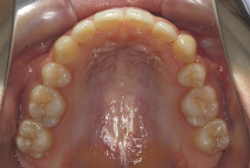

混合歯列期から治療開始した側方拡大による非抜歯症例

「配列の凸凹を治したい」という主訴で来院したケースです。診断の結果、永久歯がすべて生えそろうと、かなり厳しい叢生(歯並びの凸凹のことです)になる可能性が高いと判明しました。原因としては特に上の顎の骨が小さいため、歯を収容する容量不足になっていると診断しました。このケースの場合は、成長発育期に治療開始しますので、顎の骨を土台ごと大きくすることが可能です。

そこで、まず急速拡大装置を使用して上顎骨の拡大を行い、上顎骨の容量が拡大したことを確認後、マルチブラケット装置を使って全体の修正をする、と言う二段階の作戦をとることになりました。

この時期に使う急速拡大装置は、適切な診断に基づいて正しく使用することで確実に骨を大きくすることができます。拡大することで隙間が確保できるので、永久歯の抜歯を避けることができます。

急速拡大装置を1日1回装置の中央にある拡大ネジを、ご自身で回して頂くことで25日間くらいかけて、6mmほど拡大しました。拡大後は、上顎の前歯の隙間が広がっていることがお分かりいただけると思うのですが、土台の骨ごと広がるのでこのような隙間ができます。その後1年半くらいマルチブラケット装置を使用して、全体の修正を行いました。

結局、歯の本数を減らすことなく、すべてご自分の歯を残して正しい配列にすることができました。このケースの場合、2009年10月より拡大と経過観察を行い、2012年3月より1年2ヶ月マルチブラケット装置を装着、2013年5月に治療を終了しました。2段階で行う治療としては短期間で終了しているケースと思います。